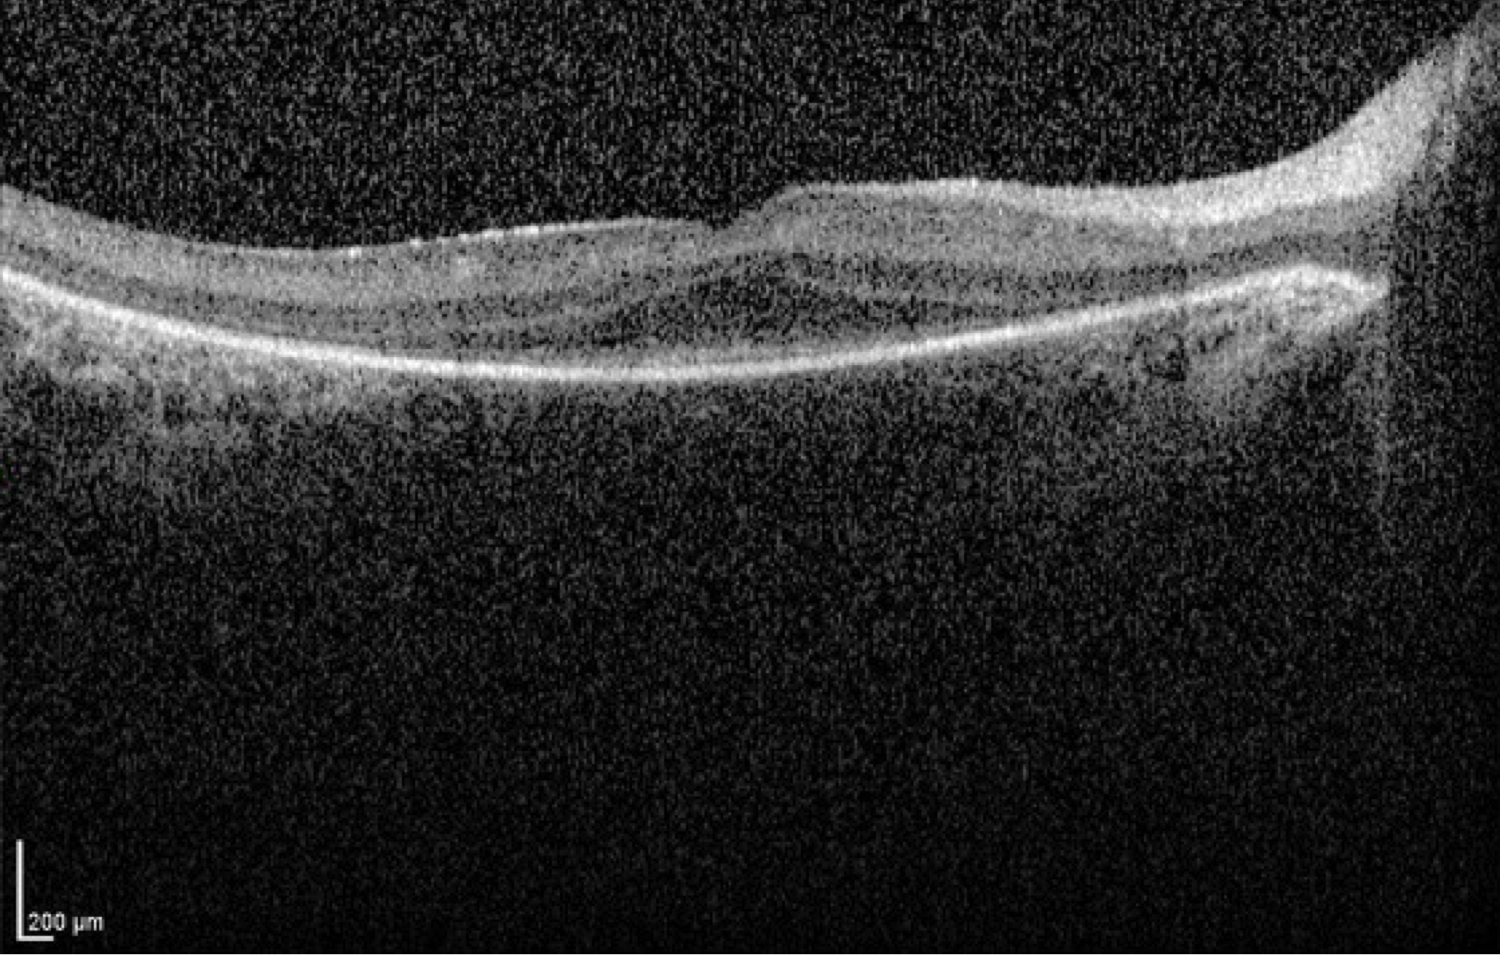

Case 9 is a six year old girl who was visually inattentive and had pronounced nystagmus at 4 months of age. An electroretinogram was performed at that time and no responses could be detected under any stimulus conditions. Her parents have normal vision. On our examination, her visual acuity was 20/80. Streak retinoscopy revealed about 5 diopters of hyperopia.

Optical coherence tomogram of the right eye.